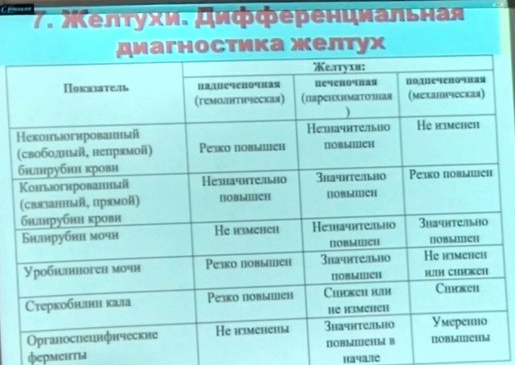

Дифференциальная диагностика заболеваний плевры